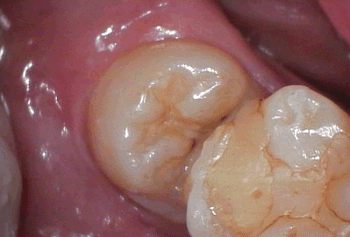

今回の「親知らず」は斜めだし、頭が出ているので抜歯はそう難しくありません!

完全な横向きだったり、骨に埋もれているとやっかいで難易度があがります!汗!

今回の斜めでもそのまま抜く事は出来ませんので、歯を「分割」します!

取出すためには「2分割」や「3分割」と分けて智恵の和のように出すのです! |